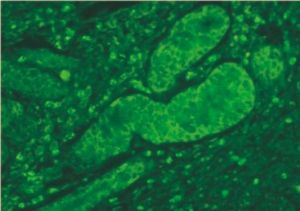

DNA探針原位雜交